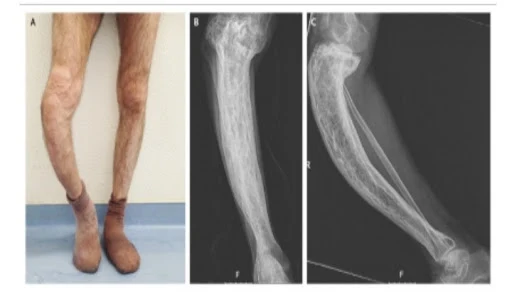

Over time the affected bones can become deformed  leading to issues like bowing of long bones such as the legs and an enlarged or misshapen skull.

Weakened bones are more prone to fractures which can occur without significant trauma or injury.

Diagnosing Paget's disease typically involves a combination of clinical assessment, blood tests to measure markers of bone turnover, and imaging studies such as X-rays  bone scans or MRI. These tests help confirm the diagnosis, assess the extent of bone involvement and rule out other bone disorders.